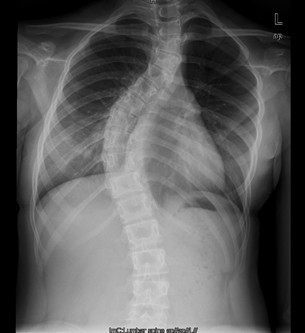

患者女,13岁,因“发现脊柱侧凸畸形4月”入院。患者4月前家长无意间发现胸背部脊柱侧凸,双肩不等高,无牛奶咖啡斑、无皮下结节,不伴活动耐力下降、气促、心悸、胸背痛、腰痛,日常活动及运动能力正常,在当地医院检查后建议手术治疗,到我院就诊,门诊以"特发性脊柱侧凸"收入住院。

查体:胸段脊柱向右侧凸,右侧胸廓后部凸起,剃刀背畸形,剃刀背高度2cm,右肩高,骨盆略向右倾斜,四肢及关节未见异常,未查见牛奶咖啡斑。脊柱各棘突及棘突旁无压痛及扣痛。胸腰部前屈、后伸及侧屈、侧旋范围正常,双下肢等长,未发现感觉减退区,四肢肌力5级,生理反射均正常引出,病理反射未引出。 辅查:X片示胸段脊柱以胸8为中心明显右侧弯畸形,胸段上段及腰段相应轻度左突侧弯。

初步诊断:特发性脊柱侧凸(Lenke:ⅡA ̄型) 诊疗计划: 拟经后路脊柱侧凸矫形+同种异体骨植骨+椎弓根螺钉内固定术术

术中见胸椎脊柱S形侧弯,肌肉韧性较差,棘突偏离中线,凹侧小关节退变明显,胸段脊柱以T8为中心明显右凸,T4为中心向左侧凸起,右侧剃刀背畸形。